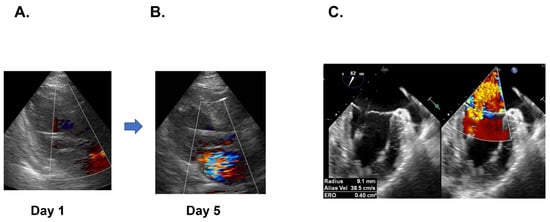

2.4. ECMO Weaning and Mitral Valve Replacement

2.5. Impella Weaning with Cardiac Recovery